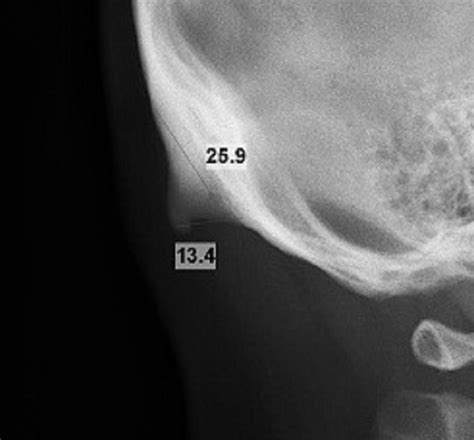

The External Occipital Protuberance (often abbreviated as EOP) is a midline projection on the outer surface of the occipital bone. If you run your fingers along the back of your head, starting from the base of your skull and moving upward toward the neck, you will likely feel this bony protrusion. It marks the transition point between the cranium and the cervical spine.

This structure is not uniform across all individuals; its prominence can vary significantly based on factors such as age, sex, and genetics. Historically, anatomists have used the EOP as an important reference point for measuring skull dimensions. Its presence is indicative of the robust musculature required to hold the human head upright, a feat that requires constant engagement from the neck and upper back muscles.